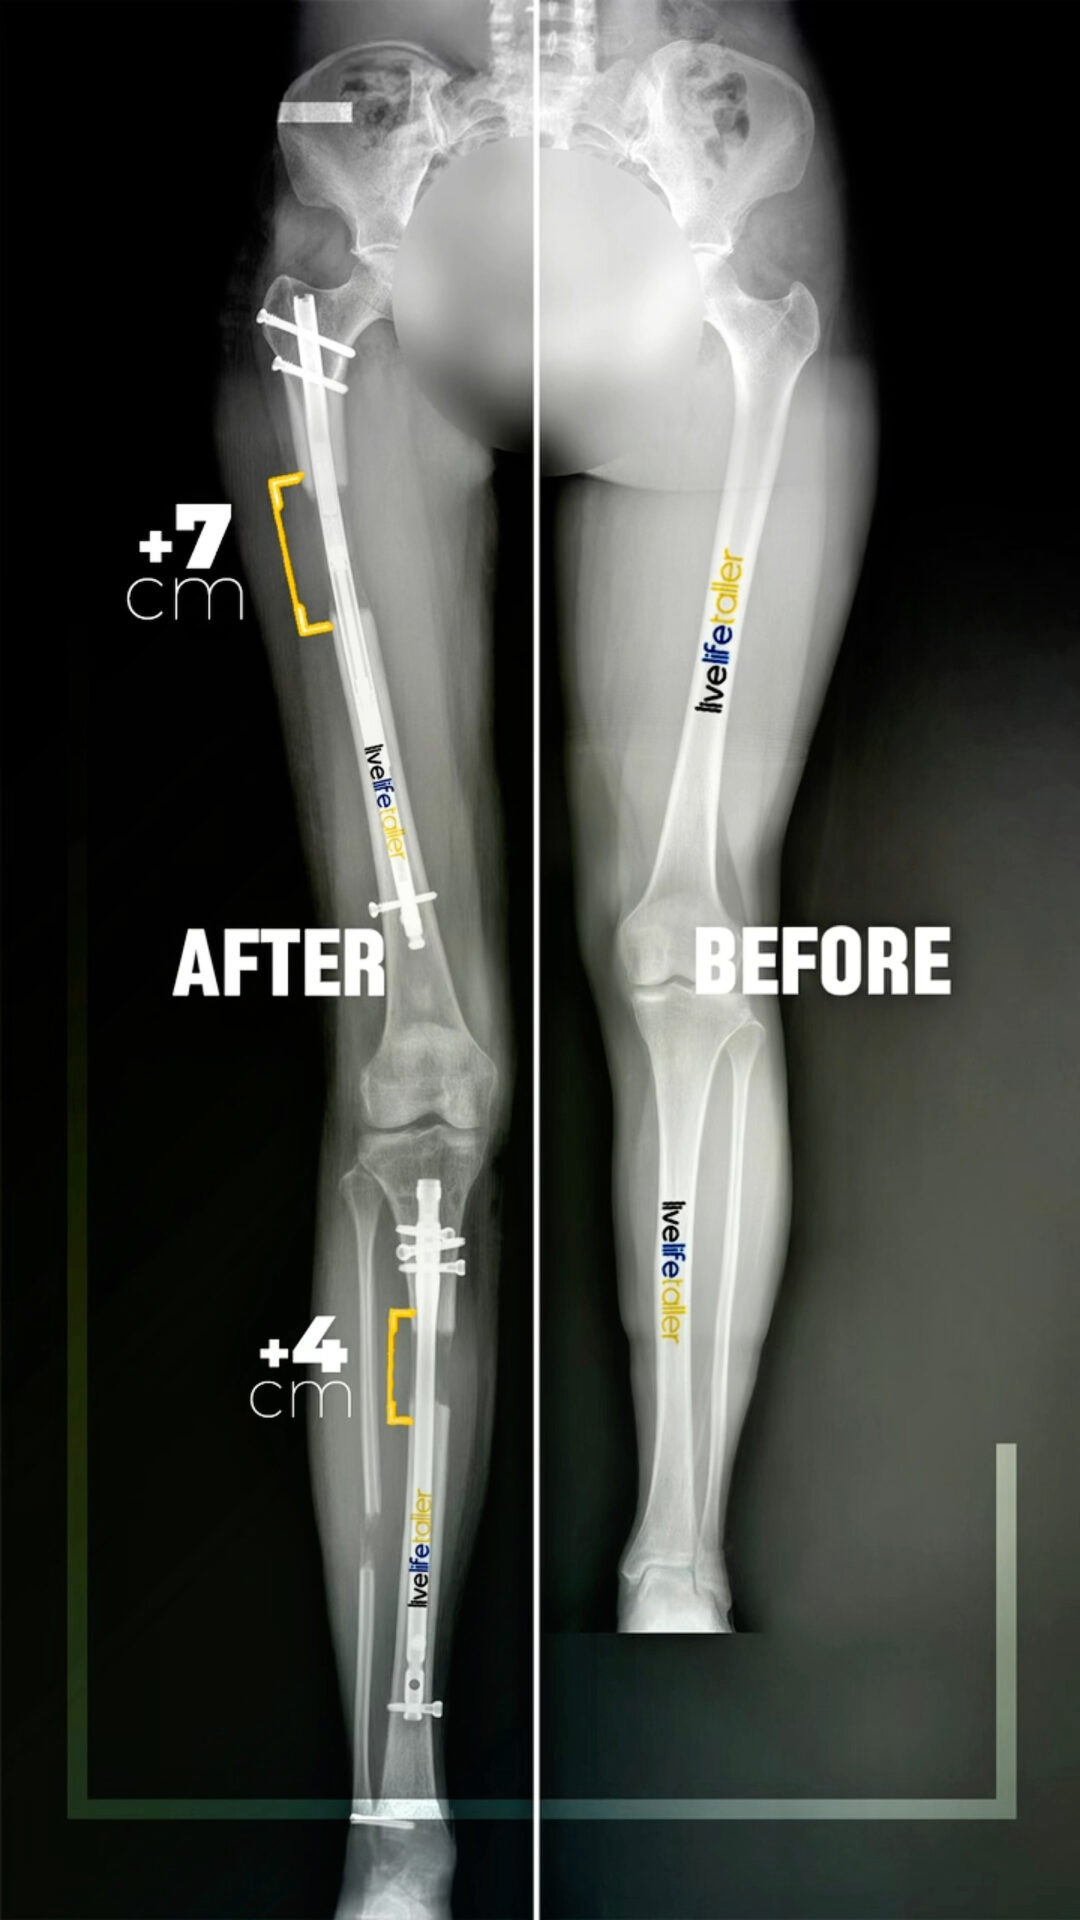

Quadrilateral Lengthening Before and After

It’s worth noting that the maximum achievable lengthening is still considered to be up to 16cm. However, the specific lengthening amounts may vary from person to person based on individual factors such as bone quality, soft tissue condition, and patient goals. As a general guideline, femur lengthening can be around 8cm, while tibia lengthening can range from approximately 6-7cm. These recommendations can be further customized and tailored to the unique needs and circumstances of each patient, with close consideration given to their overall health, functional requirements, and desired outcomes.